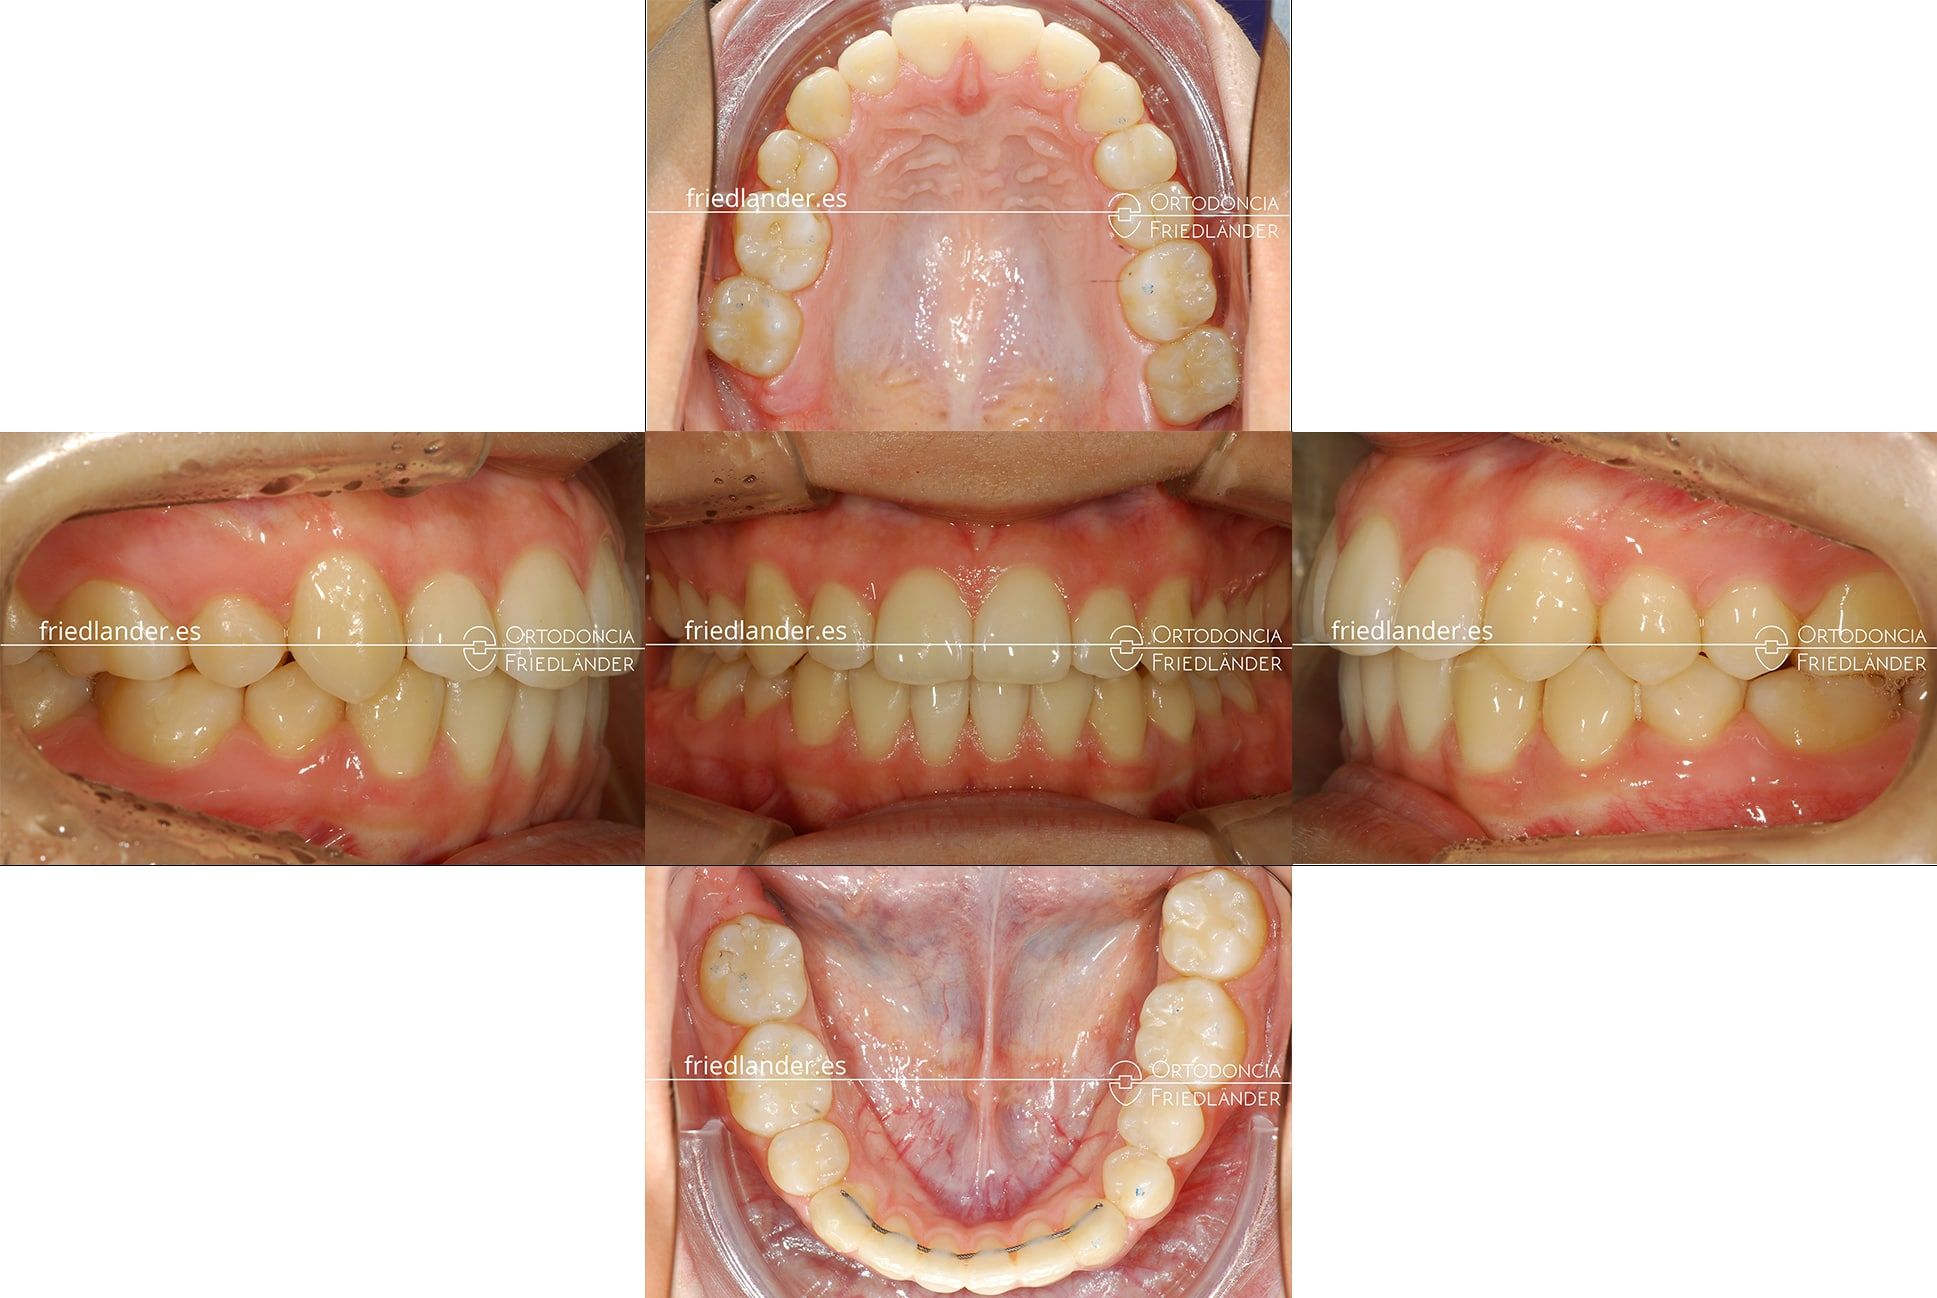

Resultados del tratamiento

La parte difícil de este caso fue el engranaje final de los dientes y la simetría entre los caninos. La paciente acabó con el tratamiento muy contenta y sus expectativas han sido cumplidos; aquí se puede ver los resultados a los 17 meses de tratamiento.

Imagen de la arcada superior donde se puede ver el desplazamiento de la línea media al centra de la arcada.